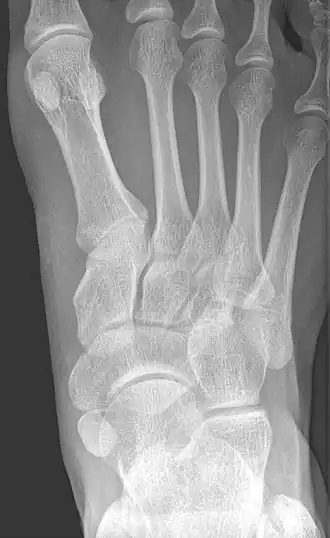

Radiological images